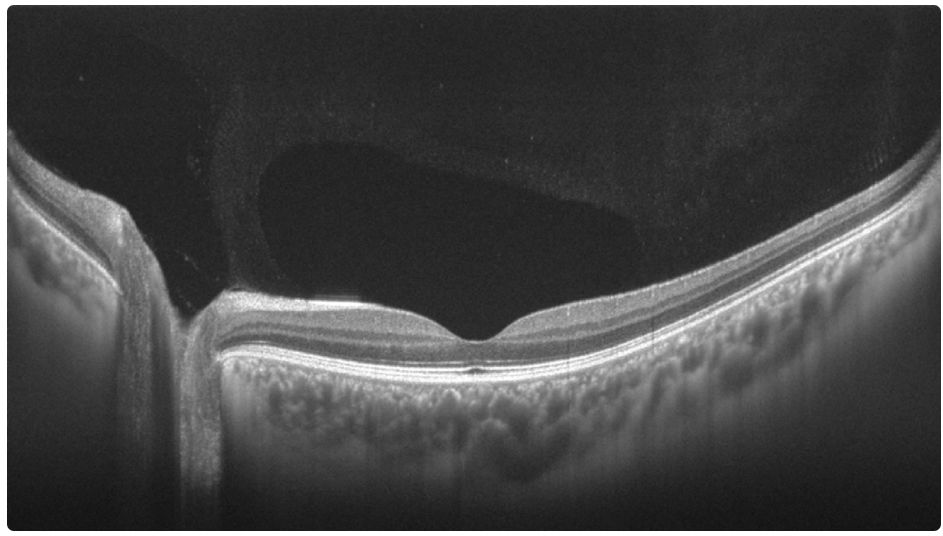

16mm视盘-黄斑区断层成像(团队供图)

- 产品:眼科扫频OCT产品性能更加完善,软件量化分析功能进一步优化升级。随着诸多底层器件技术的突破,产品成本进一步降低。OCT断层、大视场三维成像、大市场OCTA成像质量提升到最佳质量。其它多个产品线正在进行工程化研发。